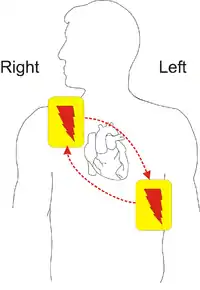

Placement

Resuscitation electrodes are placed according to one of two schemes. The anterior-posterior scheme is the preferred scheme for long-term electrode placement. One electrode is placed over the left precordium (the lower part of the chest, in front of the heart). The other electrode is placed on the back, behind the heart in the region between the scapula. This placement is preferred because it is best for non-invasive pacing.

The anterior-apex scheme (anterior-lateral position) can be used when the anterior-posterior scheme is inconvenient or unnecessary. In this scheme, the anterior electrode is placed on the right, below the clavicle. The apex electrode is applied to the left side of the patient, just below and to the left of the pectoral muscle. This scheme works well for defibrillation and cardioversion, as well as for monitoring an ECG.